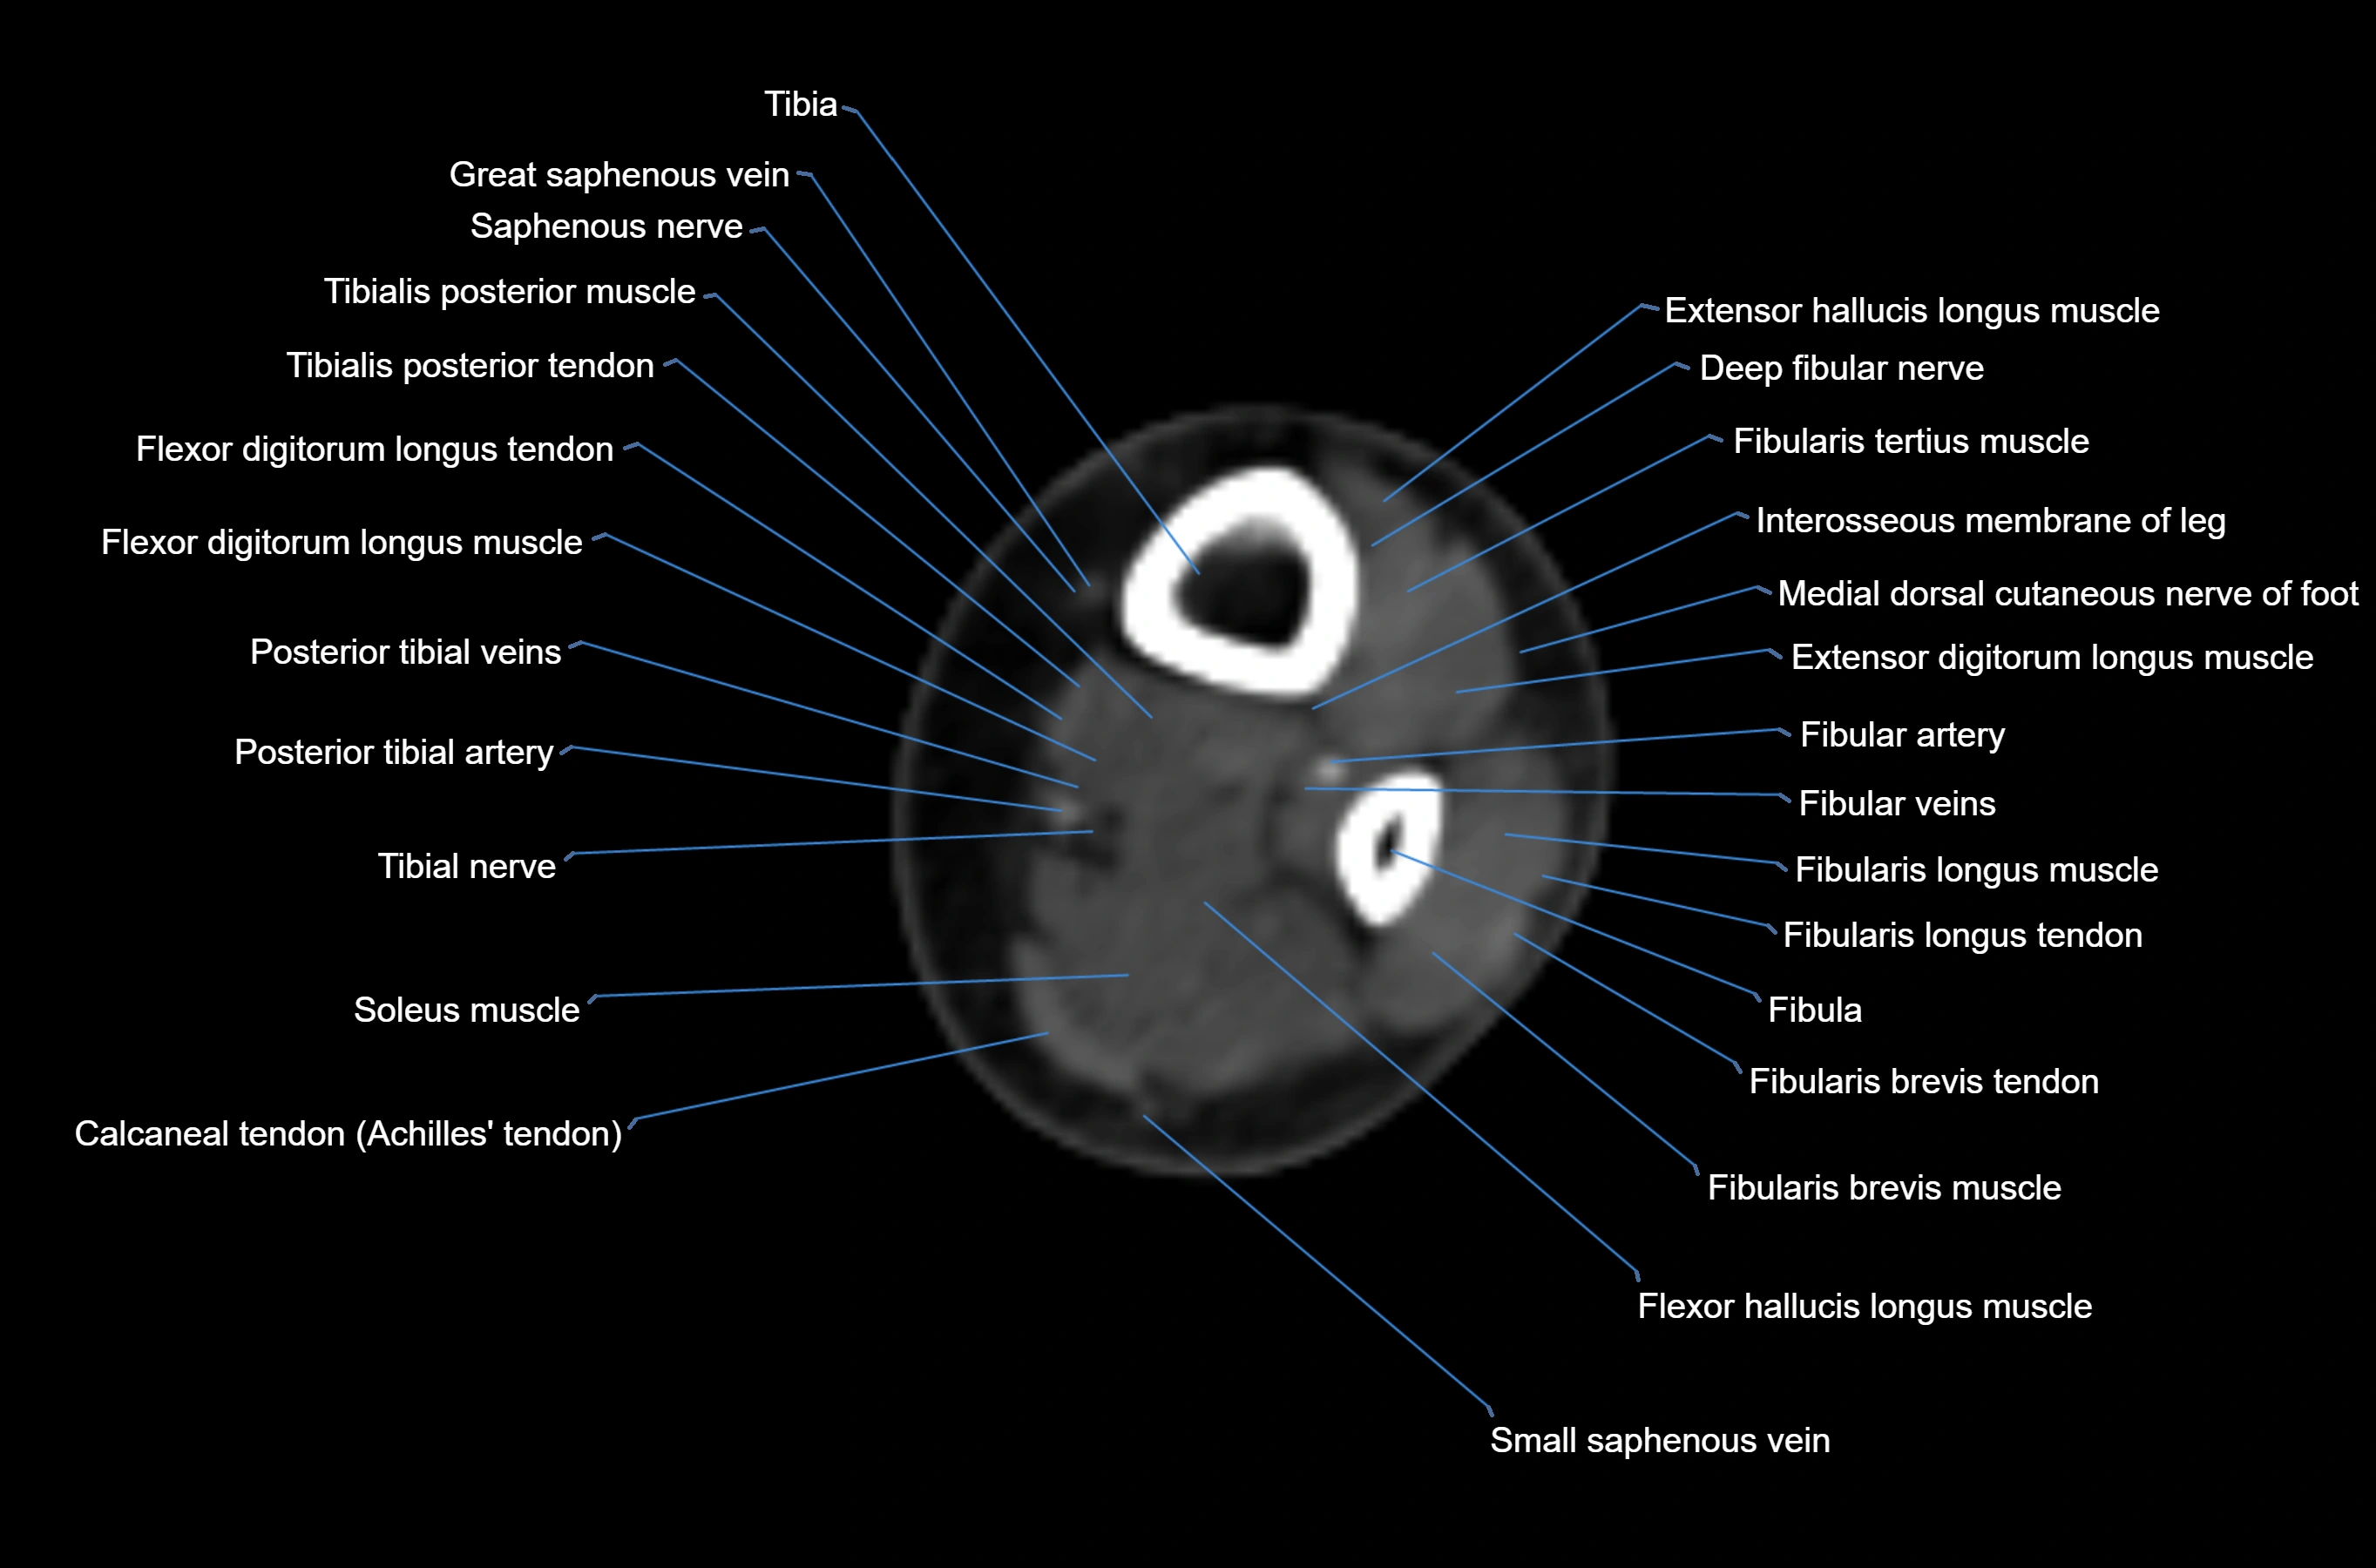

CT image